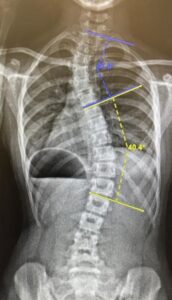

All scoliosis requiring surgery or bracing started as a mild curve, so why wait until it becomes a substantial curve with a cobb angle which is deemed to be a true scoliosis.